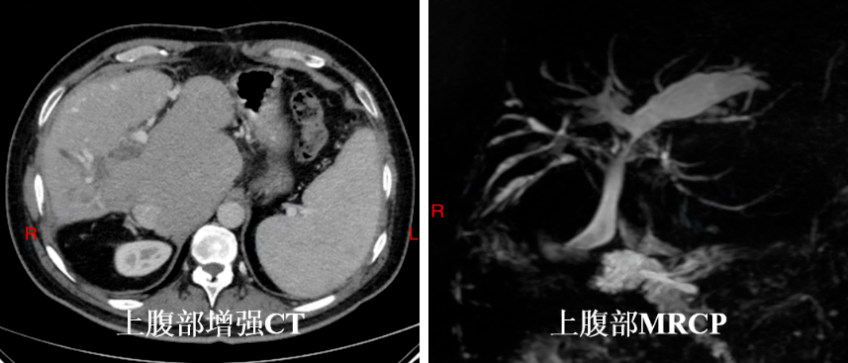

辅助检查:周先生上腹部增强 CT 提示肝脏形态异常,肝总管、胆总管显示不清,考虑术后改变;肝硬化,门静脉增宽,脾大。肝右叶斑片状弱强化影,肝内胆管扩张,肿瘤性病变可能。MRCP 示肝内胆管扩张,肝门部胆管及胆总管显示不清。实验室检查:CA19-9 86.8U/ml,CA-125 33.1 U/ml, 总胆红素 48.7umol/L,直接胆红素 30.3 umol/L。